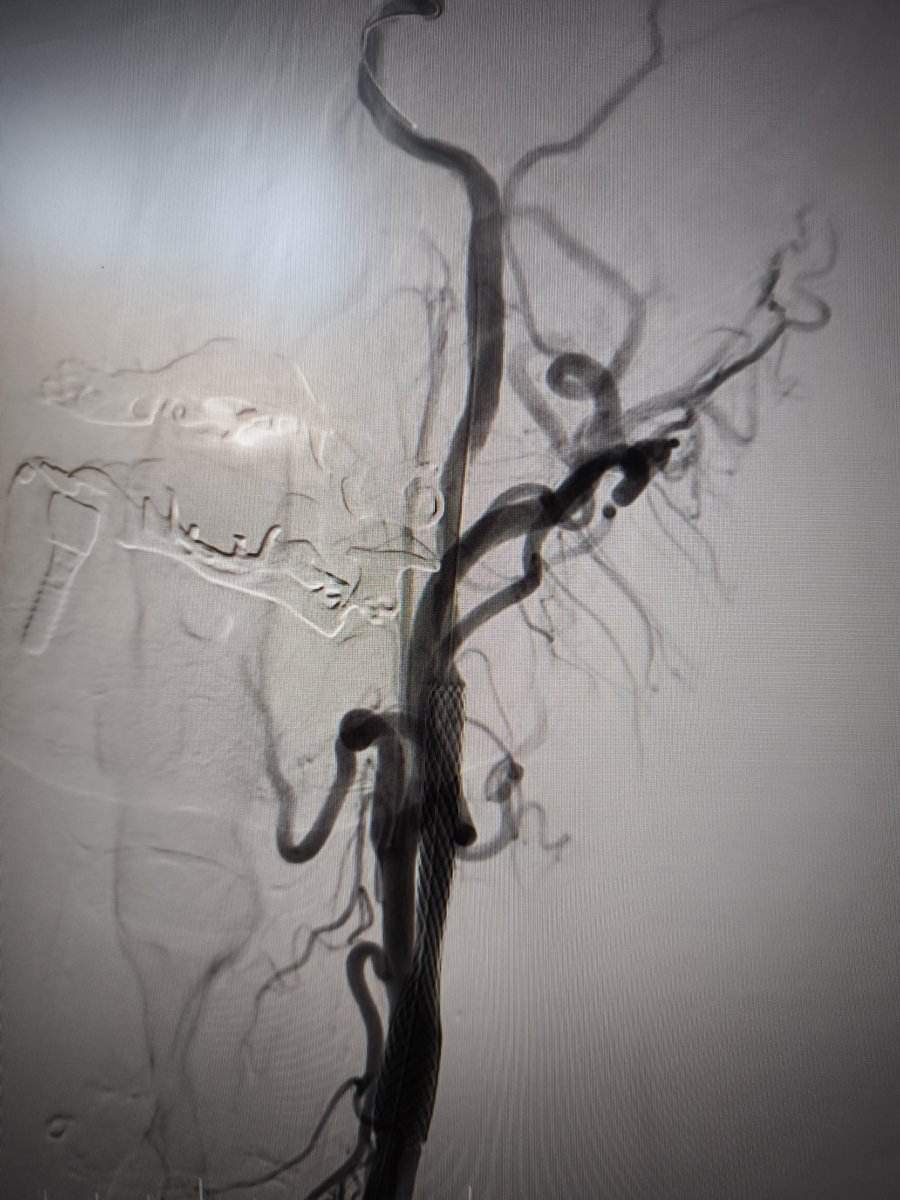

Proud to contribute to this life-saving initiative alongside Subdelegació Girona, Pere Parramon Rubio, Policía Nacional, and Fundación España Salud. Together, we're strengthening emergency response in cardiac emergencies. We are committed to helping save lives, one innovation at a time.